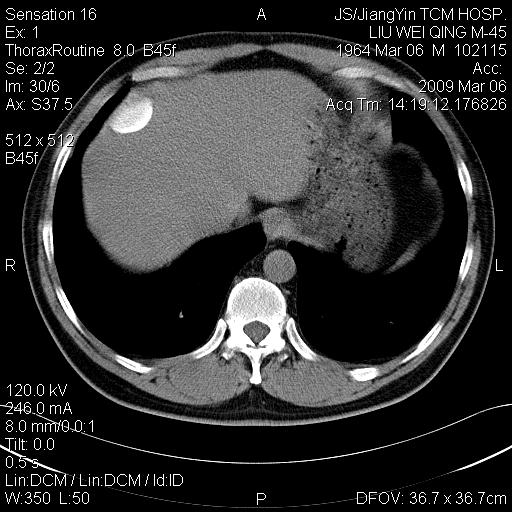

标题: CT18518:胸部扫描时发现肝边缘钙体影。请问是韧带钙化吗?

没见过。考虑肝内钙化,不象韧带钙化。

考虑肝内右外侧缘两处钙化,原因呢?(血管病变或其它)

考虑肝包膜下陈旧性包裹性积液。

考虑---局限性腹腔积液〔钙乳性〕。    一般多为炎症刺激造成局部钙乳沉着所致。

支持考虑肝包膜下陈旧性包裹性积液。

考虑肝包膜下钙化

以下是引用xulianj在2009-3-6 20:44:00的发言:[br]支持考虑肝包膜下陈旧性包裹性积液。

支持!